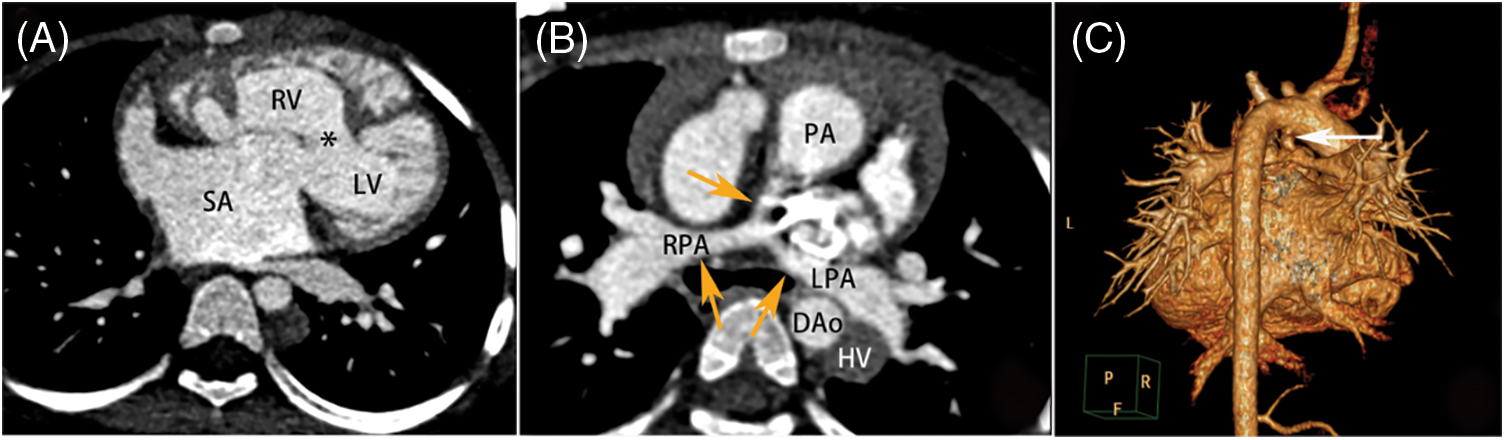

The various intracardiac and extracardiac malformations observed during surgery are detailed in Table 2. In terms of intracardiac malformation, patients with SV are most likely to be associated with atrial septal defect (33/75, 44.0%). In patients with SA, the most common abnormalities were pulmonary artery stenosis (12/24, 50.0%) and pulmonary valve stenosis (10/24, 41.7%) (Fig. 2). In SV patients, the top three malformations were patent ductus arteriosus (25/75, 33.3%), pulmonary artery stenosis (23/75, 30.7%) and right ventricular double outlet (20/75, 26.7%) (Fig. 3). In the patients with SA-SV, the incidence of pulmonary artery dilation (11/24, 45.8%), right aortic arch (10/24, 41.7%), right ventricular outflow tract stenosis (9/24, 37.5%), coarctation of aorta (9/24, 37.5%) were more pronounced (Fig. 4).

Figure 4: SA-SV in a female aged 9 years. (A) The transverse plane of a SA-SV. (B, C) The MPR and VR images show the absence of the left pulmonary artery (*) and multiple collateral circulation in the mediastinum (white arrow) (ellipse). SA-SV = single atrium-single ventricle, other abbreviations as in Figs. 1–3

We found 13 right-sided aortic arches in SV patients and 10 in SA-SV patients (p < 0.05). A total of three SV patients had coarctation of aorta, compared with six SA patients and nine SA-SV patients (p < 0.01). Pulmonary artery dilatation occurred in 11 SA-SV patients, compared with two SA patients and five SV patients (p < 0.01). The incidence of both intracardiac and extracardiac malformations was higher in patients with SA-SV than in those with SA or SV.